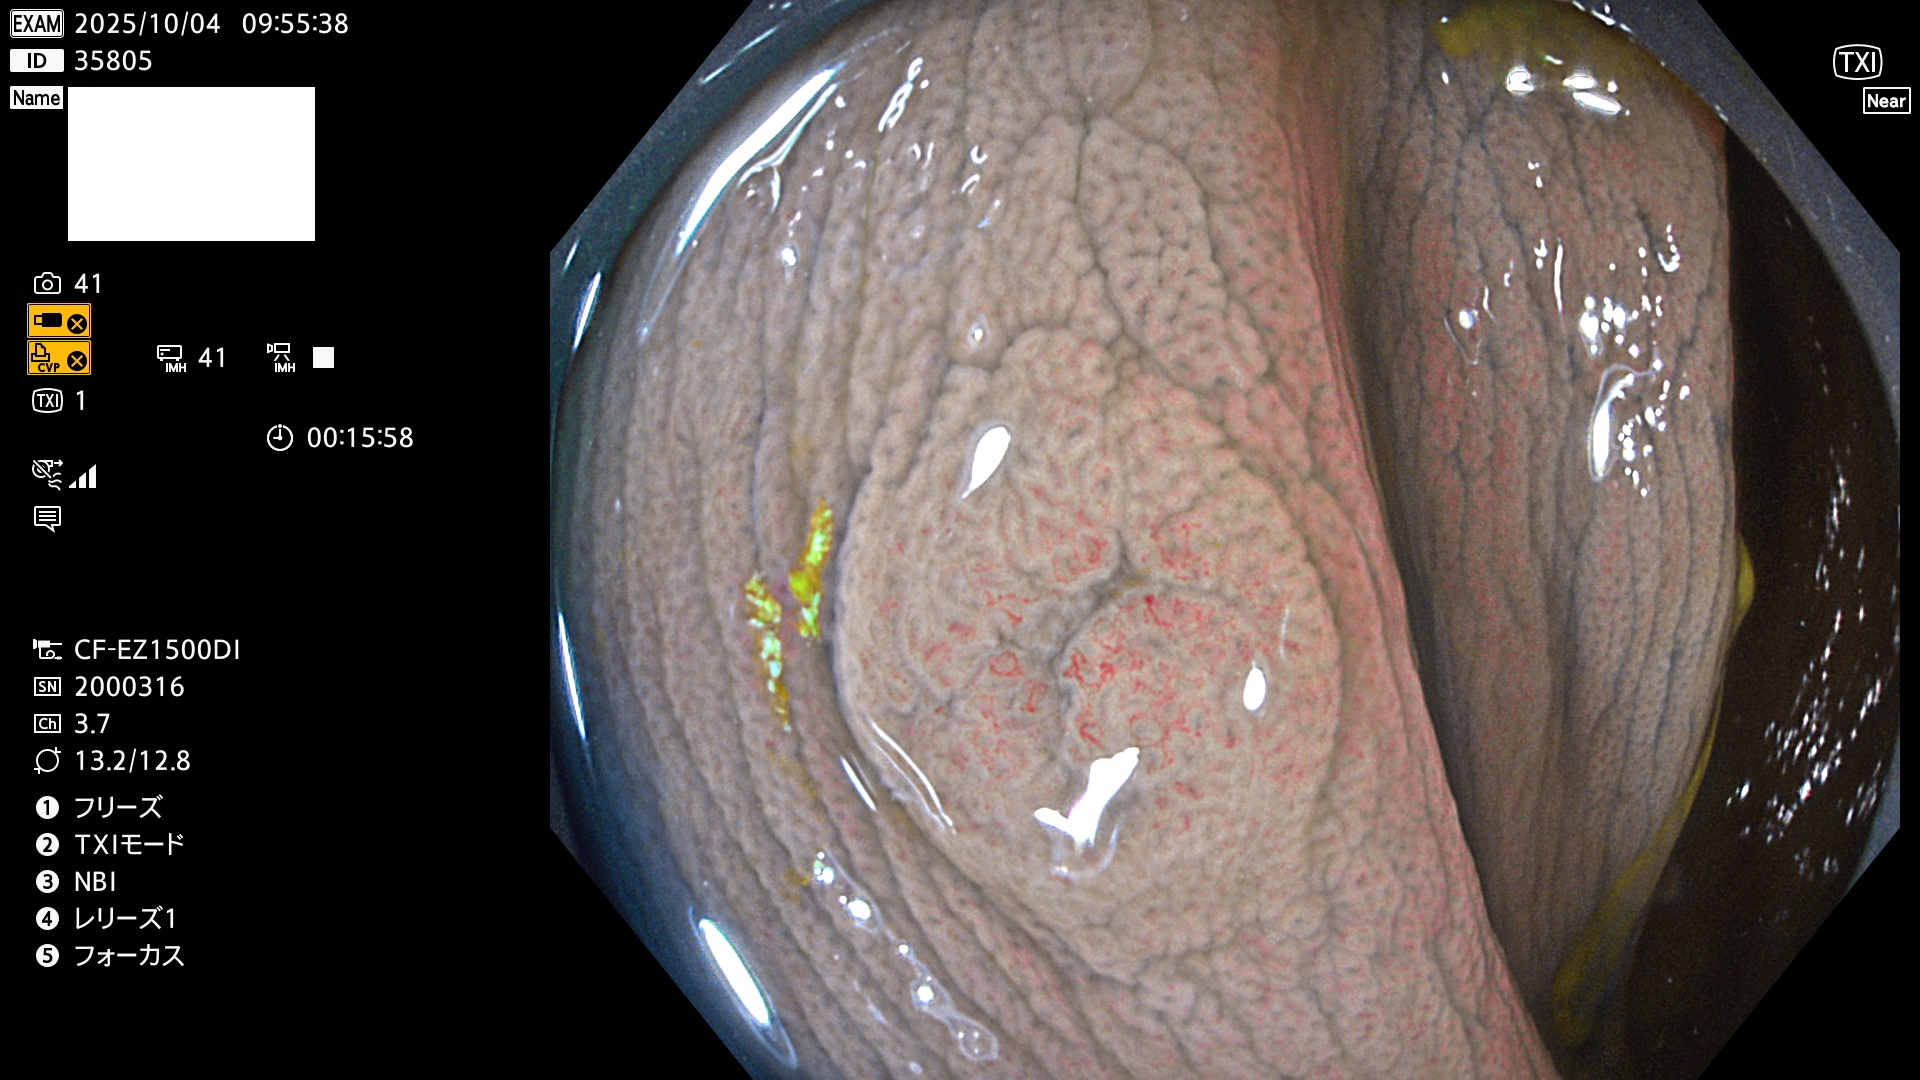

完全に平坦な物をUb、陥凹している物をUcと呼びます。Ubは認識が困難で、Ucはびらん(炎症)と紛らわしいために見落とされやすく、「内視鏡後・大腸癌」の原因になります。

専門的)Uc=De Novo癌? 内視鏡の解像度が低かった時代、このような説もありました。しかし今日の高精度内視鏡では良性の微小なUc型腺腫(APC遺伝子異常の腺腫)が日常的に見つかります。Ucこそが多段階発癌(Adenoma-Carcinoma Sequence)のMain Routeです。

毎週の検査(木・金・土・日)に発見されたUbとUc型・腺腫を、その週の日曜の夜にUPし1週間、提示します。

2025年10月2日〜10月5日の4日間(40件)で9個 (Uc_ADR=9個/40人=23%)